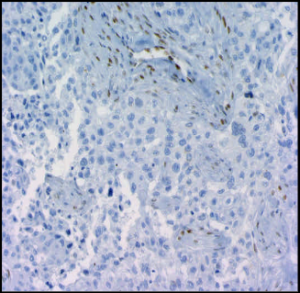

| 人乳腺腫瘤用兔單克隆抗人/小鼠ID1(Clone:195-14)(貨號:M085)染色。在內(nèi)皮細胞的核中可以看到特異性ID1染色 | 兔單克隆抗人/小鼠ID1(Clone:195-14)(貨號:M085)WB結(jié)果 |